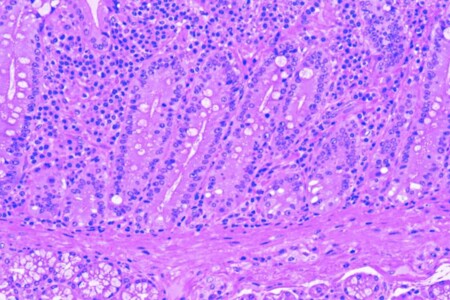

Dvanáctník je část tenkého střeva, která přispívá k trávení potravy. Částečně natrávená tekutá potrava přicházející do dvanáctníku ze žaludku obsahuje velké množství kyseliny chlorovodíkové. Zde se musí tato kyselina neutralizovat. Pokud dojde k poškození a natrávení malé plochy sliznice dvanáctníku, vzniká onemocnění zvané dvanáctníkový vřed.